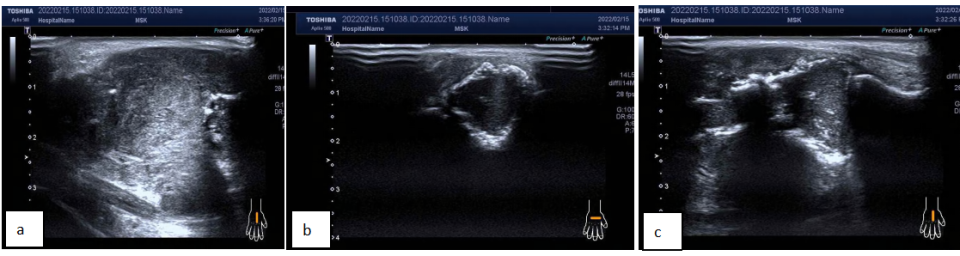

CDFI:低回声区内可见稍丰富点棒状血流信号。超声提示:右手掌背皮下不规则低回声区,第 3 掌骨骨质破坏,性质待定,考虑恶性可能,请结合其他检查。

图片图 2 右手背肿物血流信号图:内可见稍丰富点棒状血流信号

图片图 3 右侧腋窝见一个肿大淋巴结(大小 3.5 × 1.7 cm)